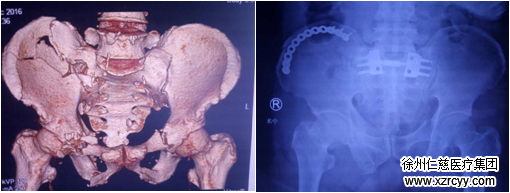

并对干骺端骨不连截骨、骨盆骨折、髋臼骨折、胫骨平台骨折、跟骨骨折等不同患者进行术前建模,利用3D制备的模型或者使用导板辅助螺钉及内固定材料准确置入,可缩短手术时间,减少并发症发生,手术效果令人满意。

betway在线登陆3D打印技术助力髋臼骨折手术